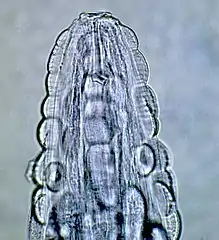

| Male Gongylonema pulchrum as seen under a light microscope.[1] | |

The morphology of the worm is as follows, from a 2000 Veterinary Medicine study: "The anterior end in both sexes was covered by numerous cuticular platelets. There was a pair of lateral cervical papillae. The buccal opening was small and extended in the dorsoventral direction. Around the mouth a cuticular elevation enclosed the labia, and eight papillae were located laterodorsally and lateroventrally. Two large lateral amphids were seen. On the lateral sides of the female's tail, phasmidal apertures were observed. The caudal end of the male was asymmetrically alate and bore 10 pairs of papillae and two phasmidal apertures."[3] The average length for male worms is 29.1 mm (1.15 in), while the average length for adult females is 58.7 mm (2.31 in). The worm is highly mobile, as observed in patients’ mouths and as evidenced by the morphological design of the worm.

These are all pictures from a single Gongylonema pulchrum male extracted from a man in France.[1]

Head